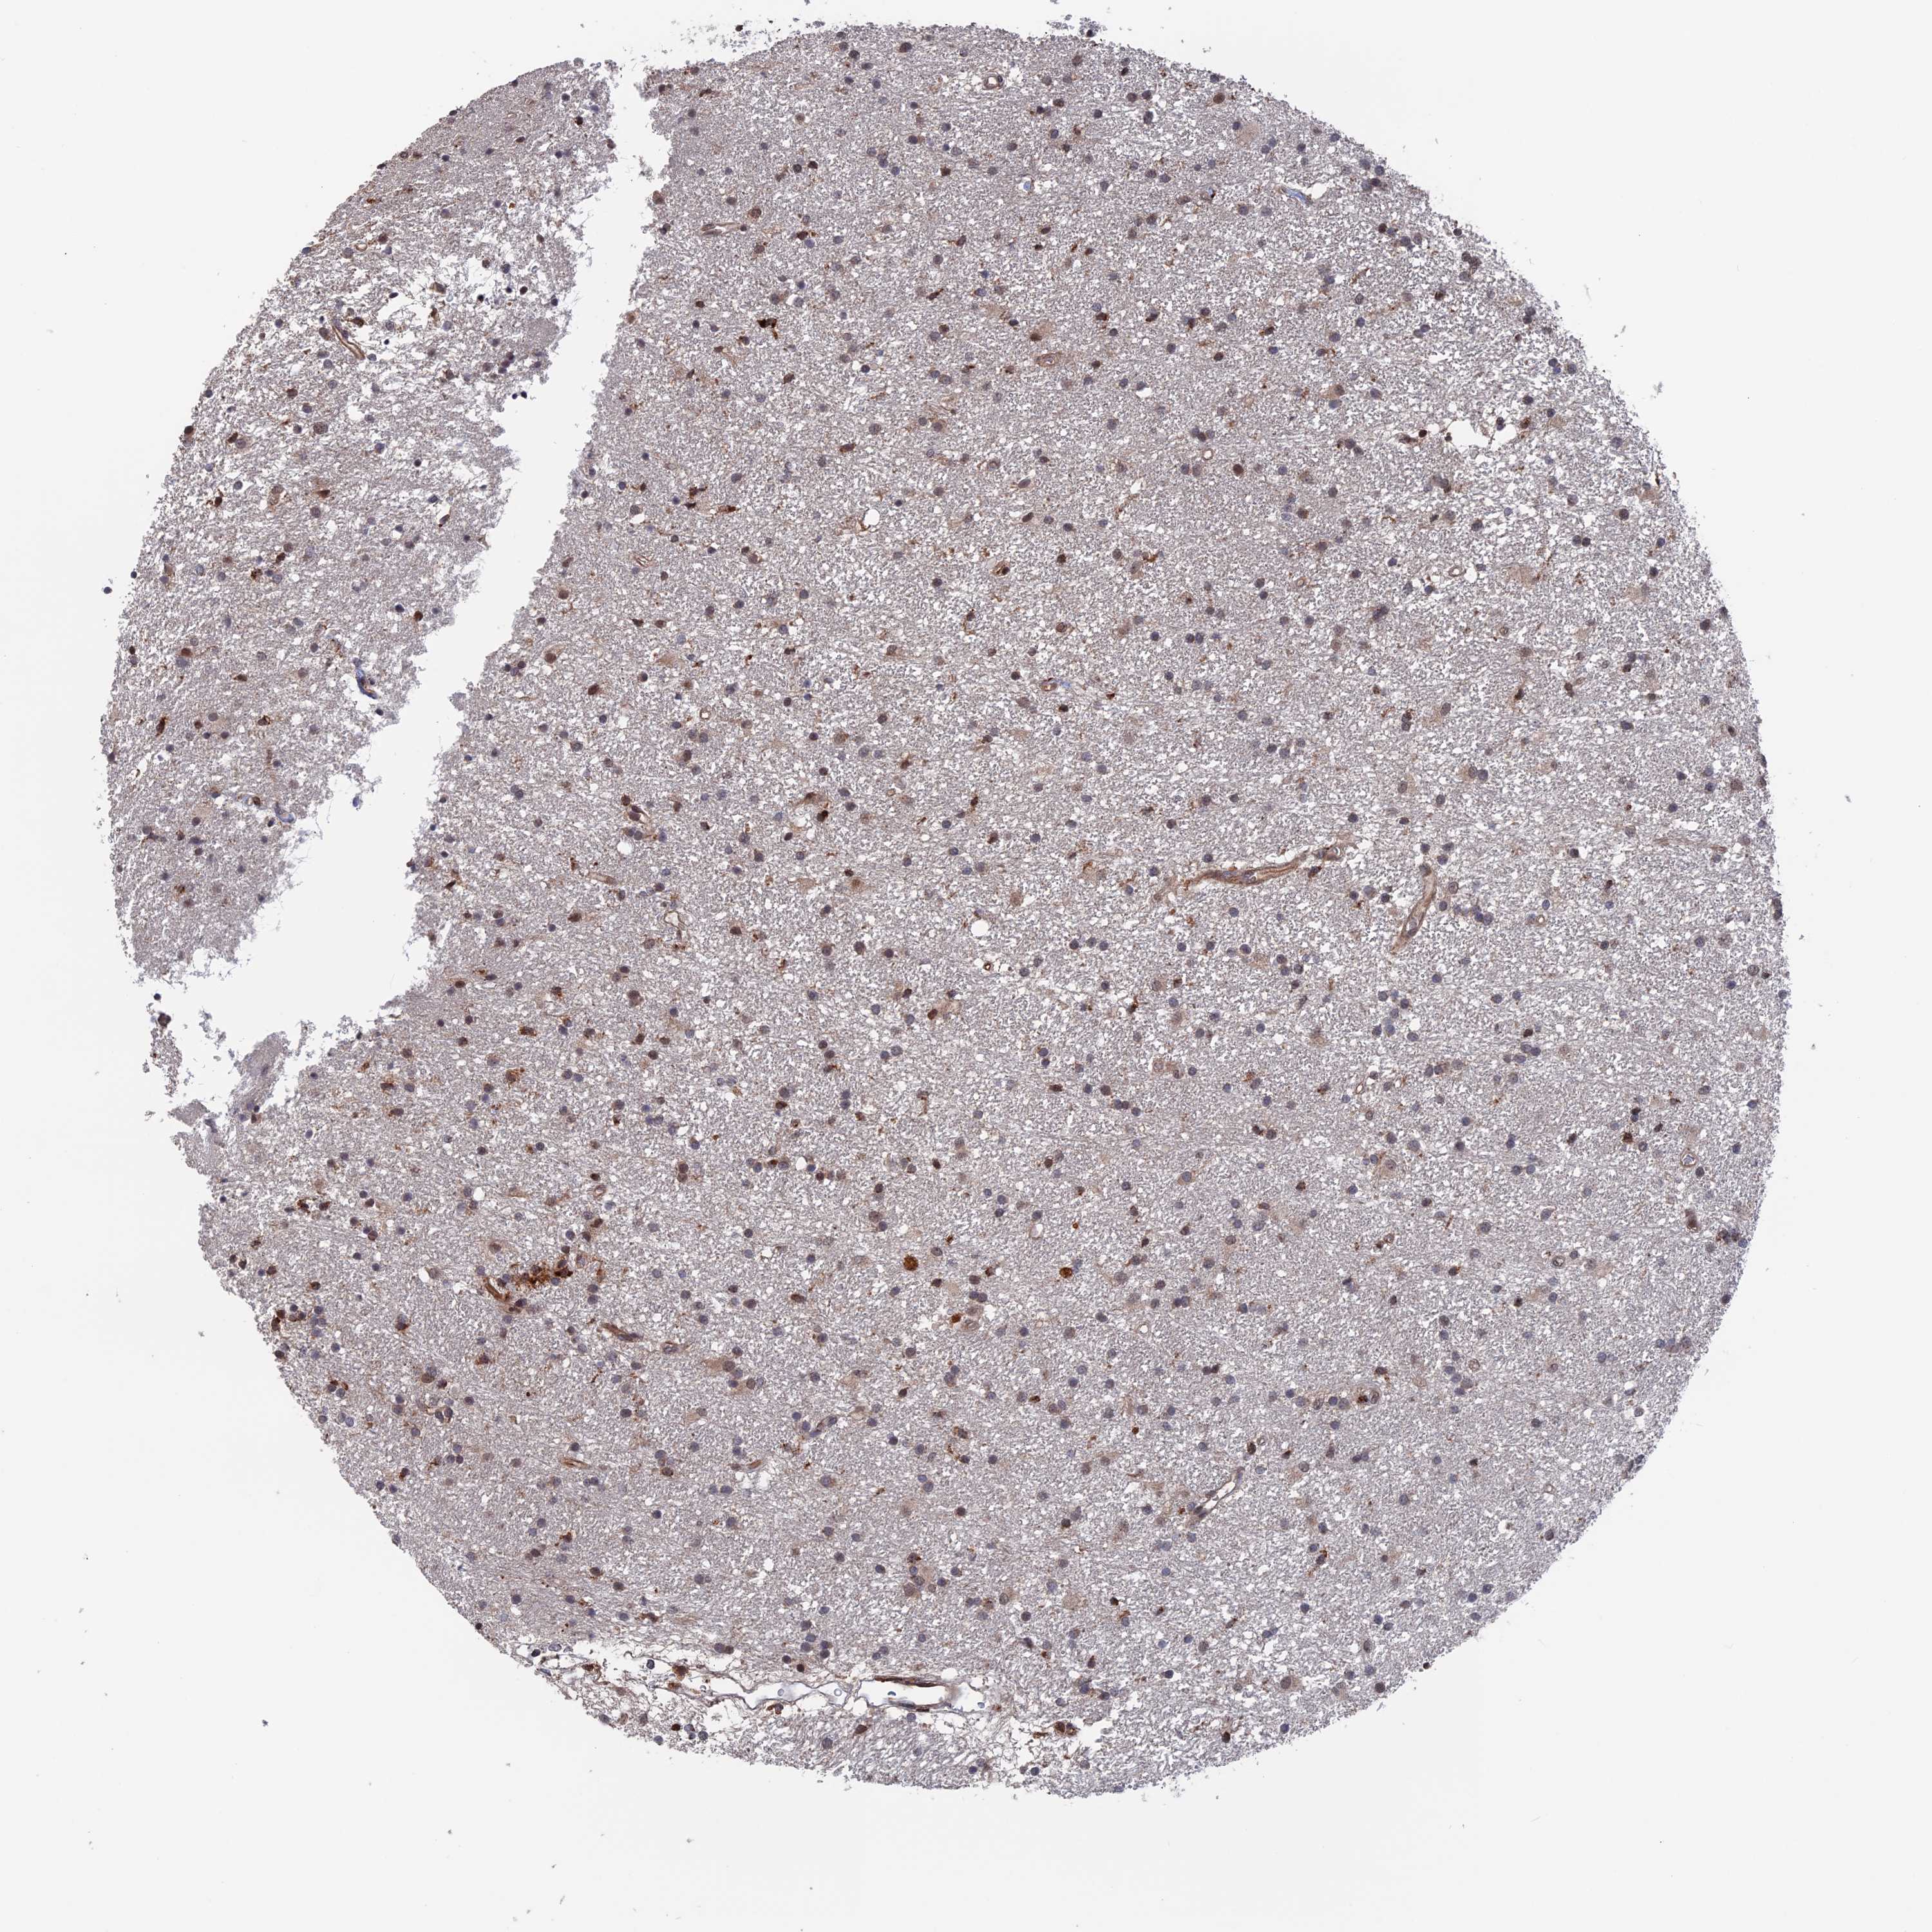

GLIOMA - Protein expressioni

A mouse-over function shows sample information and annotation data. Click on an image to view it in a full screen mode. Samples can be filtered based on level of antibody staining by selecting one or several of the following categories: high, medium, low and not detected. The assay and annotation is described here.

Note that samples used for immunohistochemistry by the Human Protein Atlas do not correspond to samples in the TCGA dataset.

Antibody stainingi

Antibody staining in the annotated cell types in the current human tissue is reported as not detected, low, medium, or high, based on conventional immunohistochemistry profiling in selected tissues. This score is based on the combination of the staining intensity and fraction of stained cells.

Each image is clickable and will lead to virtual microscopy that enables deeper exploration of all samples and also displays staining intensity scores, fraction scores and subcellular localization as well as patient and tissue information for each sample.

Antibody HPA041702

Antibody HPA041727

Staining

High

Medium

Low

Not detected

Intensity

Strong

Moderate

Weak

Negative

Quantity

>75%

75%-25%

<25%

None

Location

Nuclear

Cytoplasmic/membranous

Cytoplasmic/membranous,nuclear

Glioma, malignant, High grade

Glioma, malignant, Low grade